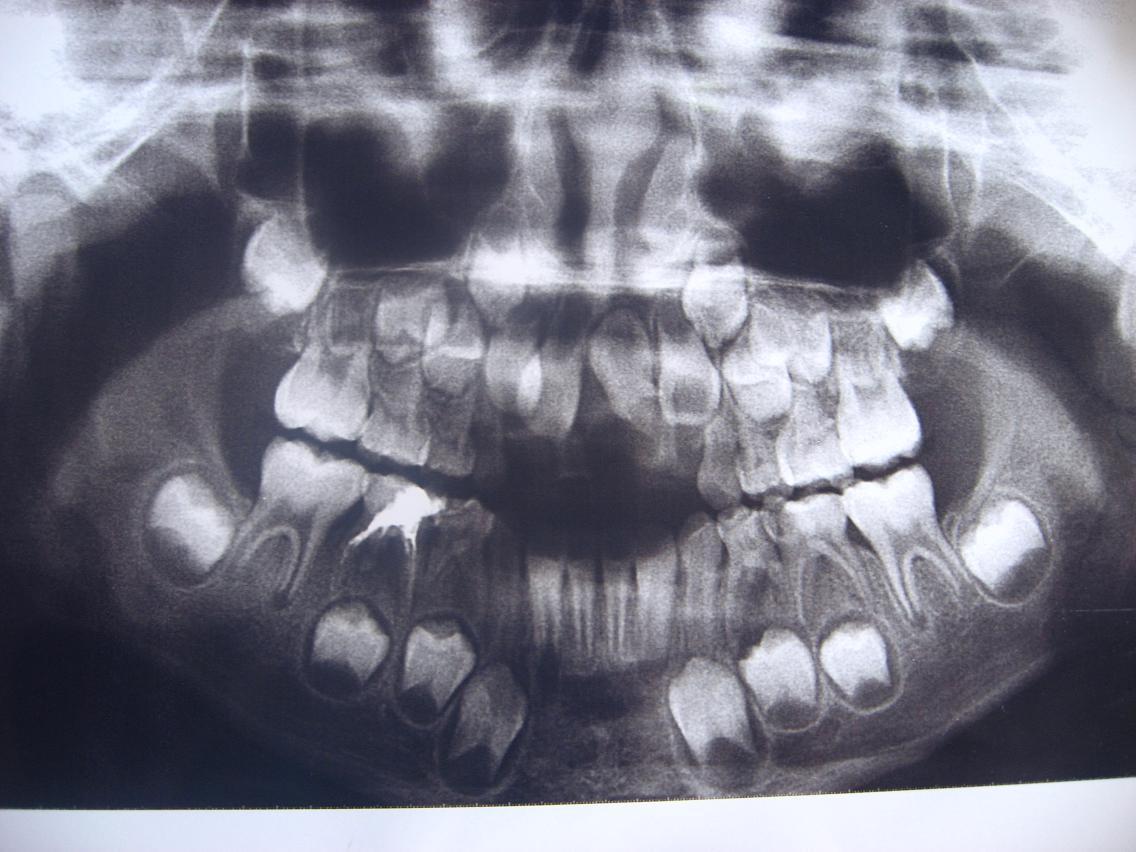

这是一个换牙期的颅骨,看起来确实有点让人难以接受。、

这个能看出乳牙还包裹着恒牙的小牙胚,经常给宝宝做牙齿检查非常重要。

不知宝宝看到这些扫描图会如何感想,一定会非常害怕看到自己的牙齿,要给宝宝养成每天刷牙、漱口的好习惯,抓好这次换牙的机会保护好牙齿。